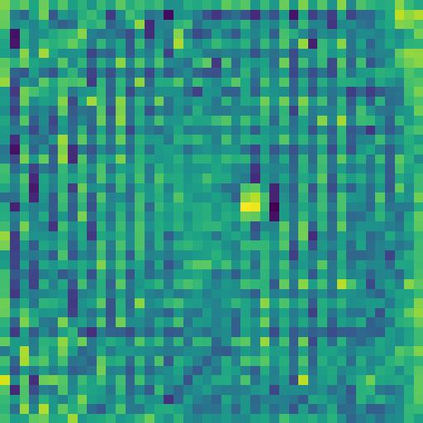

Skin lesion segmentation from dermoscopy images is of great significance in the quantitative analysis of skin cancers, which is yet challenging even for dermatologists due to the inherent issues, i.e., considerable size, shape and color variation, and ambiguous boundaries. Recent vision transformers have shown promising performance in handling the variation through global context modeling. Still, they have not thoroughly solved the problem of ambiguous boundaries as they ignore the complementary usage of the boundary knowledge and global contexts. In this paper, we propose a novel cross-scale boundary-aware transformer, \textbf{XBound-Former}, to simultaneously address the variation and boundary problems of skin lesion segmentation. XBound-Former is a purely attention-based network and catches boundary knowledge via three specially designed learners. We evaluate the model on two skin lesion datasets, ISIC-2016\&PH$^2$ and ISIC-2018, where our model consistently outperforms other convolution- and transformer-based models, especially on the boundary-wise metrics. We extensively verify the generalization ability of polyp lesion segmentation that has similar characteristics, and our model can also yield significant improvement compared to the latest models.